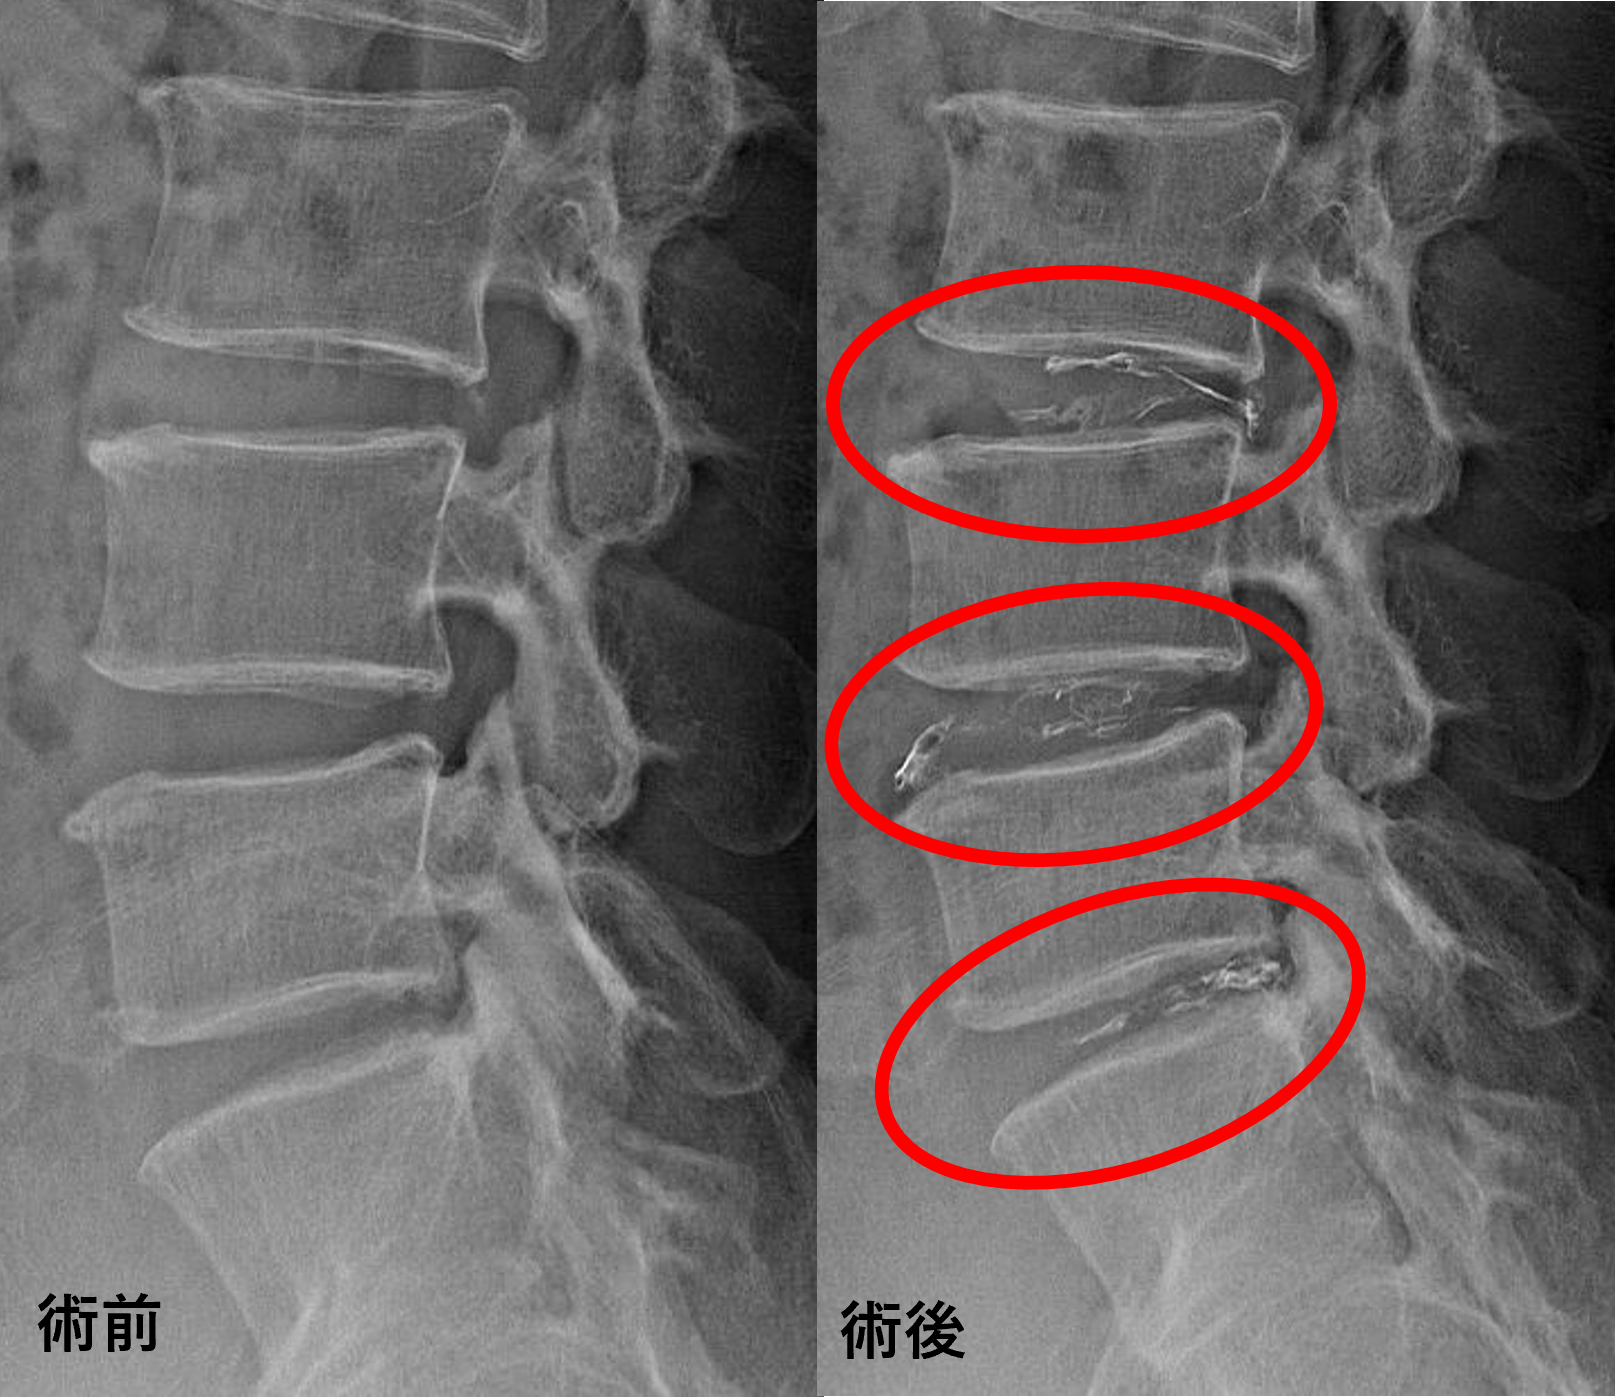

画像及び所見について

- L3/4、4/5 – 椎間板変性、膨隆、椎間孔狭窄

- L5/s – 椎間板変性、椎間板ヘルニア、椎間孔狭窄、終板変性

以上のことが画像上認められました。

L3/4、4/5、5/sの椎間板所見による脊柱管の圧排が、症状の原因の可能性が高い。

患者様と相談の元、L3/4、4/5、5/sにセルゲル法を施行